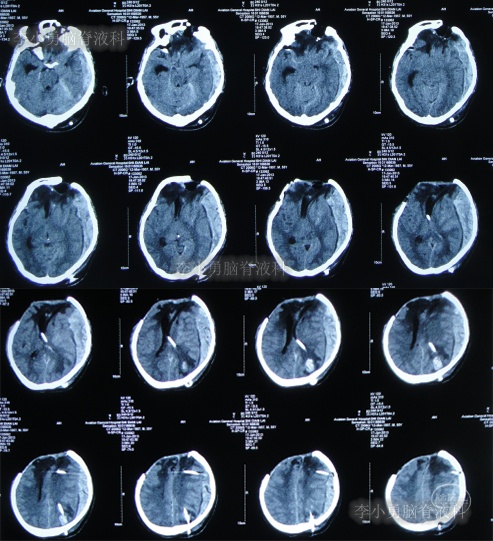

第3家医院出院后26天即2012年9月26日(开颅术后92天),因患者失语、嗜睡、吞咽障碍,第2次住入第3家医院,入院后2天即2012年9月28日,给予伤口及脑内脓肿清创缝合术+脑脊液漏修补术+右大腿取脂肪术,但术后2周即2012年10月12日,复查头颅CT提示脑积水(图-1)。

图-1:2012年10月12日头颅CT

2012年10月16日(第3家医院第2次住院20天),进行了脑室腹腔分流术(图-2)。

图-2:2012年10月16日头颅CT

脑室腹腔分流术后7天即2012年10月23日,患者突发意识丧失、双眼上翻伴头部抖动近20分钟后自行缓解,查头颅CT(图-3)后考虑为“颅内感染”。

图-3:2012年10月23日头颅CT

脑室腹腔分流术后11天即2012年10月27日,进行了脑室腹腔分流管腹腔端外置术(图-4),术中可见清亮脑脊液流出。

图-4:2012年10月27日头颅CT

治疗期间给予腰穿脑脊液检查未见细菌,但白细胞、蛋白偏高,体温仍间断升高,最高38.6度,期间查头颅CT示脑室仍有扩张(图-5)。

图-5:2012年10月30日头颅CT